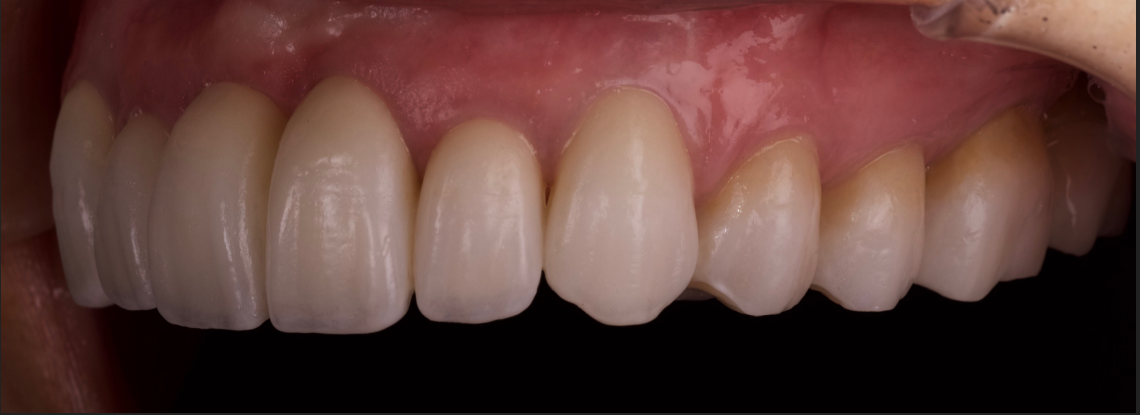

術後です。

アンテリアガイダンス、オクルーザルストップと犬歯の隆線の位置を遠心にもっていく事でイコライザーを効かせ顎関節の安定を図っております。

この治療の一番のポイントは

1つも神経をとらず、象牙質をも触らず、下の歯はほぼノンプレップ(削らない)でラミネートで仕上げています。上も元々クラウンになっていた奥歯、及び前歯以外はラミネートべニア(削らない)です。

この型取りとレントゲンが証拠になります。エナメル質を残しています。

だから、長持ちします。

「歯を削らず、神経を残す」

その上での審美です。